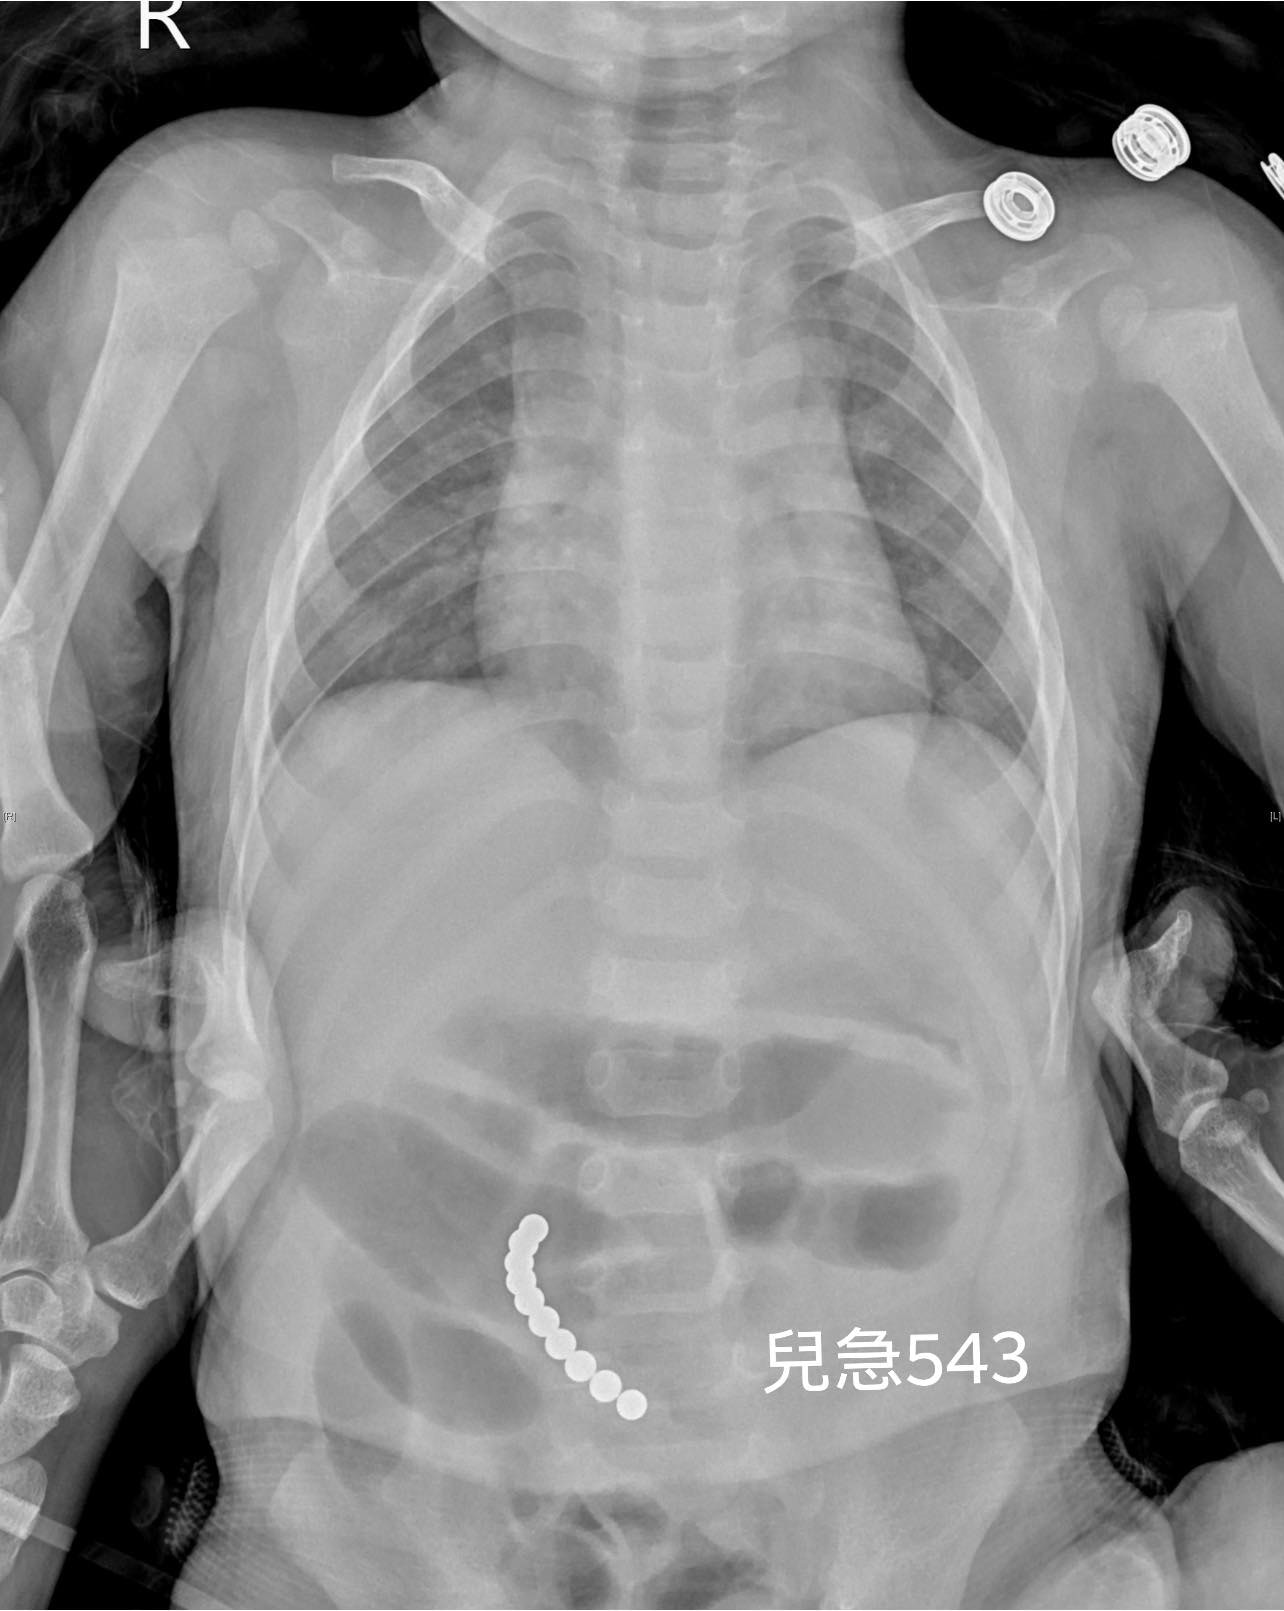

磁力玩具誤食風險主要來自於玩具中小顆粒的強力磁性磁珠(如巴克球),若兒童誤吞兩顆以上,磁珠會在腸道內互相吸附,可能夾住腸壁,導致腸穿孔、腸壞死,甚至腹膜炎、敗血症,嚴重時可能致命。

在台灣,已有多起兒童誤食磁力球送醫案例,且因磁力強大,胃鏡等醫療手段常難以取出。磁力玩具因體積小且磁性強,容易被幼兒誤食,造成嚴重腸胃道傷害。